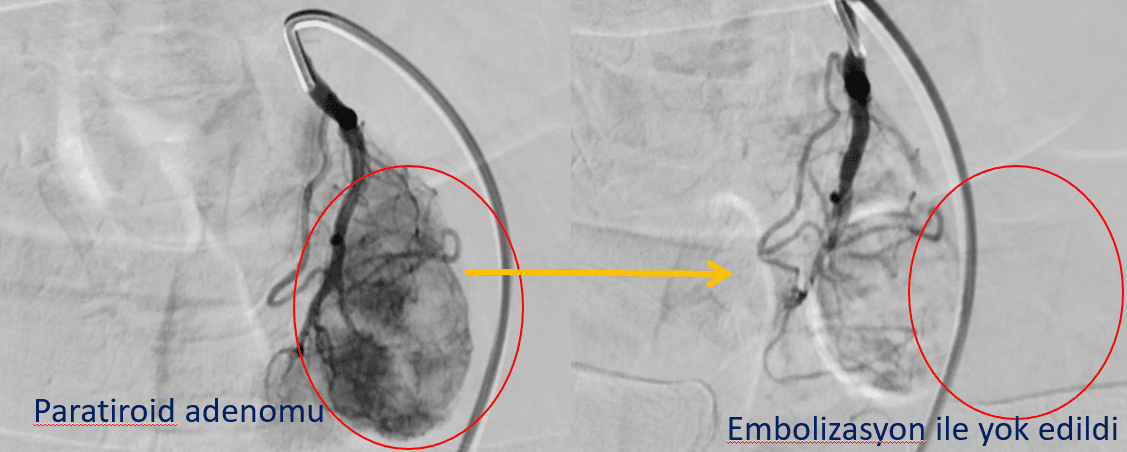

Sol akciğer komşuğuna gizlenmiş ameliyata ve ablasyona uygun olmayan paratiroid adenomu anjiyoda tespit edildi ve 15 dakikada beslenmesi tamamen durduruldu. PTH 8 gün sonra normalleşti